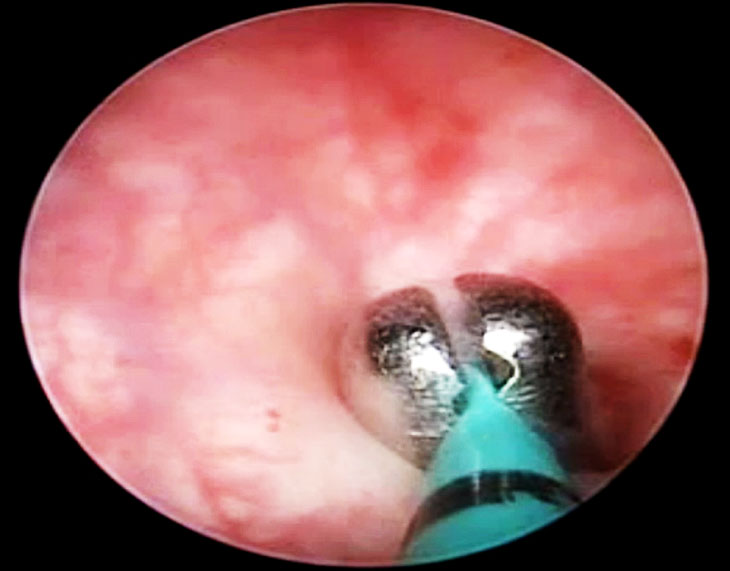

Risk of bladder injury is particularly increased in patients with a history of cesarean section. This risk can be minimized using the lateral window technique (Figure 7) in which, after dissecting the round ligament and uterovesical peritoneal fold, the laparoscopist stays above the uterine artery and adequately displaces the bladder to safely secure the artery and avoid injury.

In the correct plane, the bladder can be pushed below the cervix without needing extensive separation from the vagina, thereby reducing the risk of bleeding. In the event of a bladder injury, a two-layer closure (Figure 8) is recommended, after which the primary surgery can be continued.

7

Lateral window technique for identification of the uterine artery and ureter in a patient with previous cesarean section.